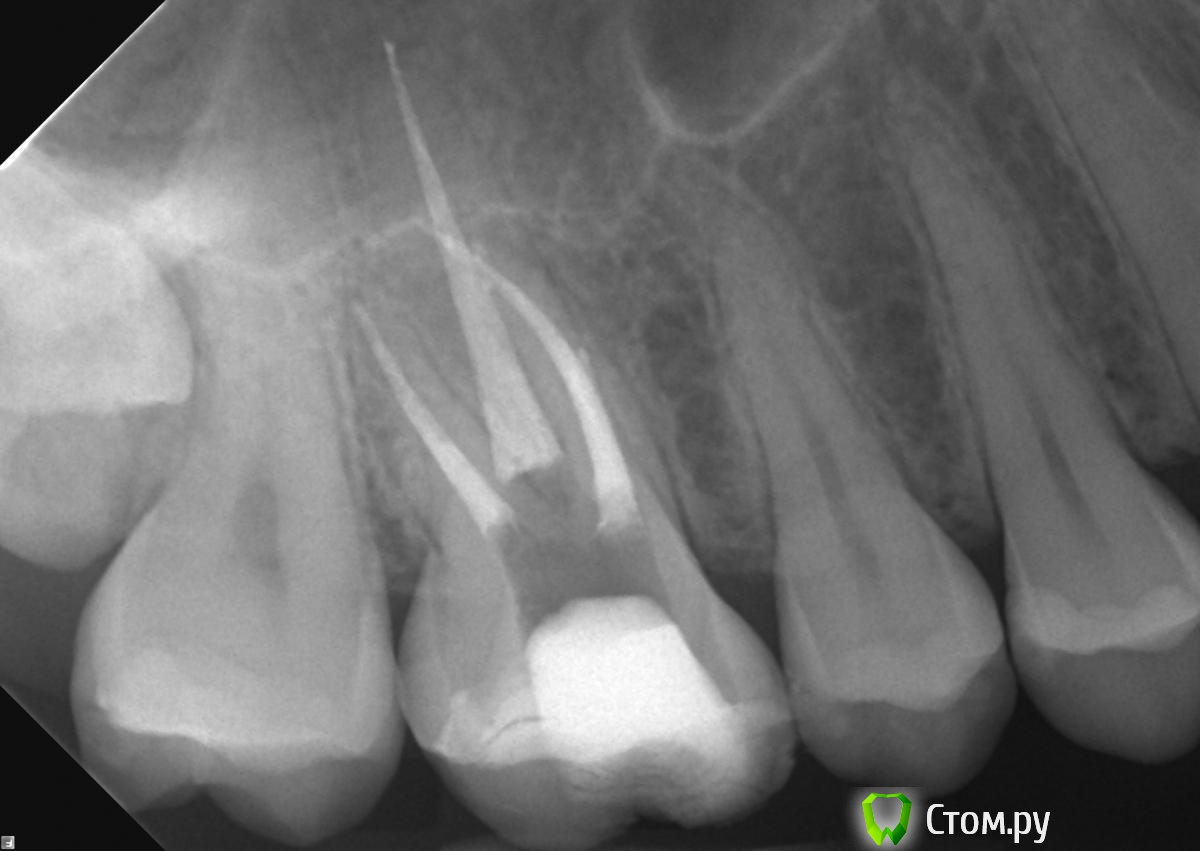

celovek Опубликовано 30 июня, 2014 Поделиться Опубликовано 30 июня, 2014 Буду очень благодарна за мнения специалистов по прилагаемой перелеченной 6-ке, с которой нужно что-то делать. Что бы вы порекомендовали? Огромное спасибо! Ссылка на комментарий

celovek Опубликовано 30 июня, 2014 Автор Поделиться Опубликовано 30 июня, 2014 прикрепите оба снимка-до и после перелечивания. Возможно Вы их перепуталиСпасибо, поищу снимок "до", но вряд ли он у меня есть. Зуб резорциненный, поэтому каналы, видимо, не удалось пройти (с микроскопом). Причем мне было сказано, что лечение проведено успешно и сумму я заплатила огромную за эту работу. Но надо как-то завершить лечение. Ссылка на комментарий

celovek Опубликовано 30 июня, 2014 Автор Поделиться Опубликовано 30 июня, 2014 Спасибо, поищу снимок "до", но вряд ли он у меня есть. Зуб резорциненный, поэтому каналы, видимо, не удалось пройти (с микроскопом). Причем мне было сказано, что лечение проведено успешно и сумму я заплатила огромную за эту работу. Но надо как-то завершить лечение.да, снимок "до" у меня только на рентгентовской пленке (не уверена, что его можно сканировать) Снимки, которые делал перелечивавший врач, мне не предоставлены. Прикрепленный снимок "после" делала в другом месте уже. Сейчас надо решить, ставить ли на это коронку и сколько она может прослужить. Ссылка на комментарий

DokDent Опубликовано 30 июня, 2014 Поделиться Опубликовано 30 июня, 2014 Спасибо, менять уже поздно. Теперь приходится расхлебывать последствия. А лечил, как бы, опытный эндодонтист, который работает уже в другой клинике. Мне жаль тех, кто может попасть в его руки. Но вроде он теперь не лечит, а заведует. Как бы на работу под микроскопом непохоже. Ну если только доктор работал с завязанными глазами. Больше похоже что зуб прорезорцинили сейчас. На переднем щёчном корне уже имеются изменения,поэтому надо пытаться перелечить Ссылка на комментарий

celovek Опубликовано 30 июня, 2014 Автор Поделиться Опубликовано 30 июня, 2014 Как бы на работу под микроскопом непохоже. Ну если только доктор работал с завязанными глазами. Больше похоже что зуб прорезорцинили сейчас. На переднем щёчном корне уже имеются изменения,поэтому надо пытаться перелечить да, это отдельная история, как он там работал. Посоветуйте, пожалуйста, что делать в моей ситуации? Снова искать специалиста с микроскопом? В клинике мне сказали, что еще одно вмешательство ни к чему уже не приведет. Лучше поставить коронку, посколько в таком виде зуб находится уже почти год. Ссылка на комментарий

felicidade Опубликовано 30 июня, 2014 Поделиться Опубликовано 30 июня, 2014 Celovek, я не врач, но занимаюсь сейчас тем же, чем и вы: перепломбировкой своих ранее безобразно запломбированных каналов.Покажу вам 2 рентгена: до перепломбировки у эндодонта с микроскопом и, соответственно, после. Мне, как неспециалисту, разница между моим финальным рентгеном и вашим очевидна. Ссылка на комментарий